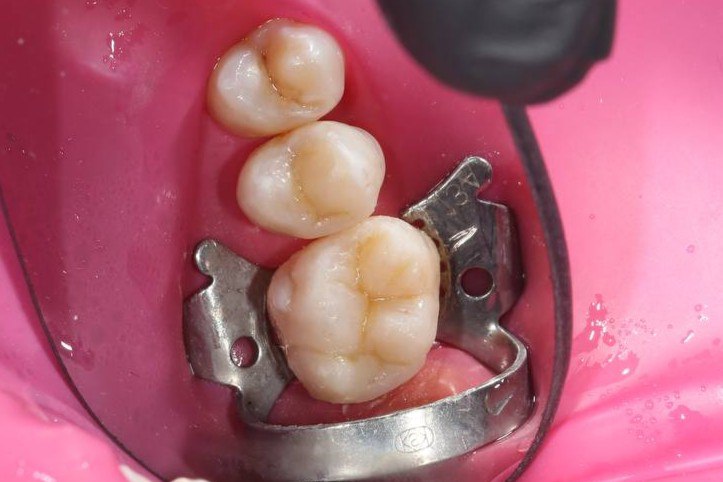

- Композитні пломби

Композитні пломби використовуються для відновлення пошкоджених або каріозних зубів. Вони виготовляються з матеріалів, які ідеально імітують натуральний колір зуба, що дозволяє досягти максимально естетичного вигляду навіть у тих місцях, де пломба не повинна бути помітною.

- Реставрація зубів

Реставрація зубів із використанням сучасних матеріалів допомагає відновити зуби після травм або великих дефектів. Це дозволяє повернути зубам їхню функціональність та естетичний вигляд.